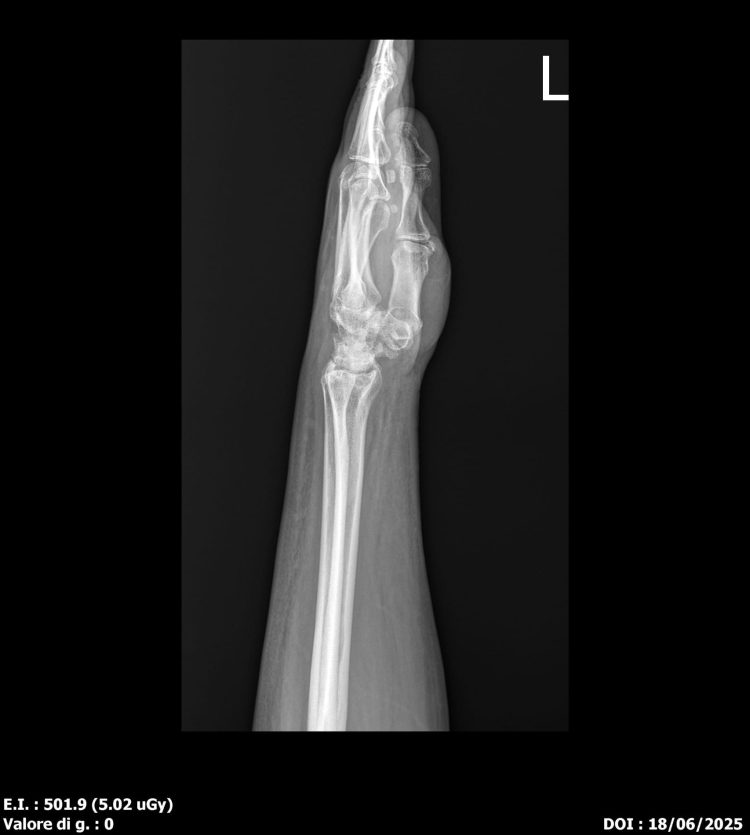

Dalla valutazione radiografica emerge una netta differenza rispetto all’esame di marzo, i segni tipici dell’artrosi risultano ridotti a giugno.